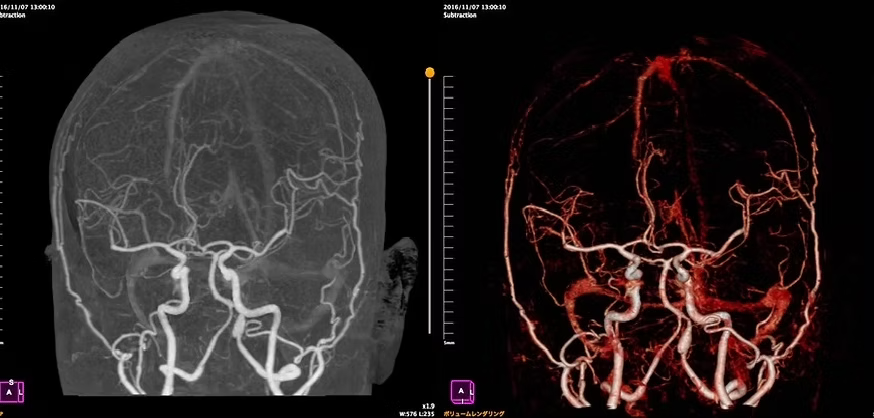

アンギオ装置

肘や太ももの付け根の動脈からカテーテルと呼ばれる細い管を挿入し、造影剤という薬剤を流し込みながら X 線撮影を行うことで、血管の状態や、流れを観察する検査です。

これにより血管にできたコブ(動脈瘤)、血管の狭窄、血管奇形、腫瘍などをより正確に把握し、今後の治療方針の検討を行います。

当院のアンギオ装置Artis zeeはフラットパネル血管造影システムにより、従来装置と比較して約50%の被曝量削減を実現しています。また3D撮影することにより的確な画像を提供することができます。

脳血管画像

脳血管3D画像

頸部血管画像

脳血管内治療WovenEndoBridgeデバイス(WEB)